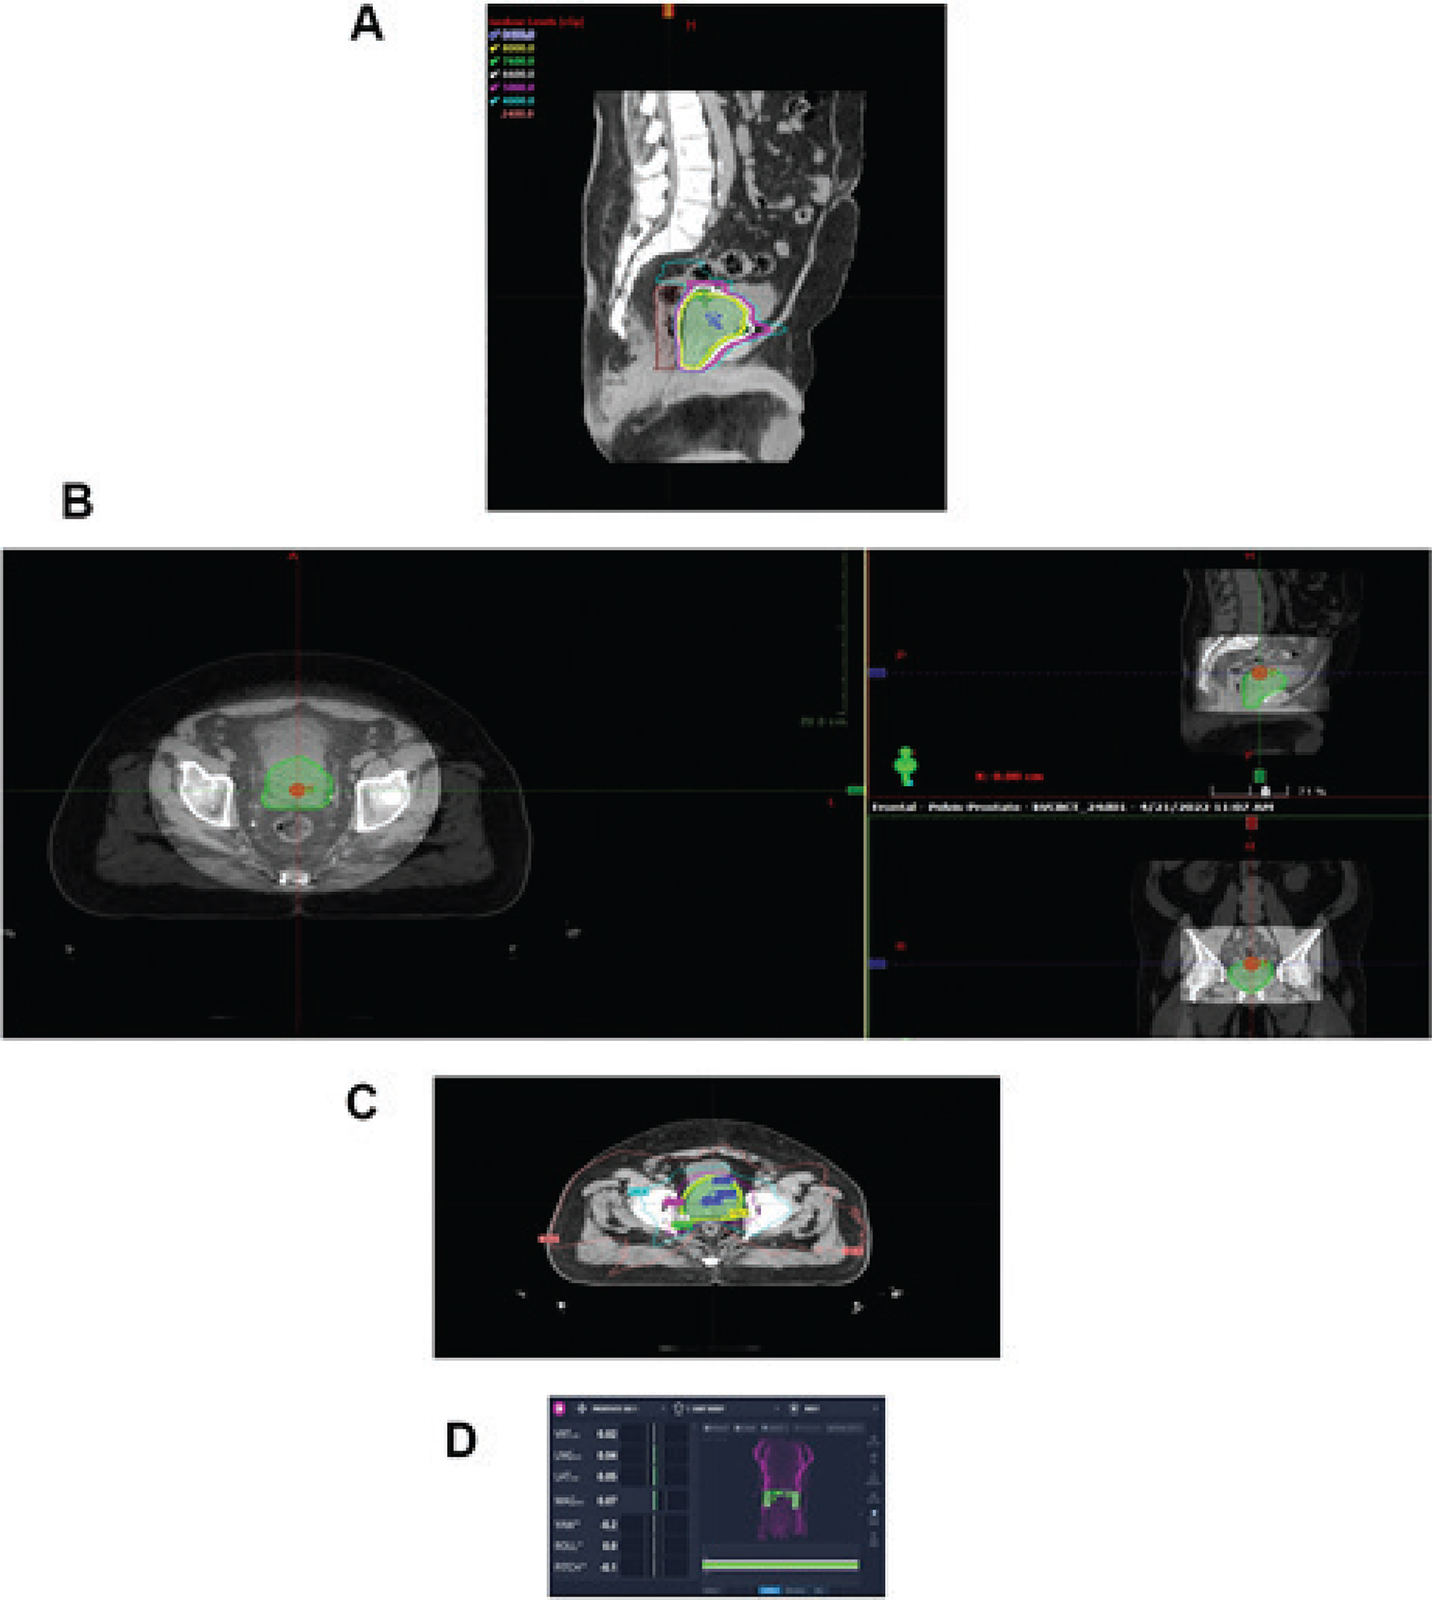

Radiation therapy after prostatectomy remains an important component of patient care. Although surgery remains an important option for patient care in prostate cancer management, often surgeons are confronted with more challenges than anticipated with extracapsular spread of tumor, lymph node involvement, perineural invasion, Gleason grade, and seminal vesicle invasion; all these are indicators of risk for local regional recurrence of disease. Although debate continues as to when to intervene with radiation therapy post-operatively, many in the radiation oncology community feel treatment is more efficacious earlier in the disease process (2326). In contrast, many in the urology community prefer to defer referral of the patient to radiation oncology until there is continuous elevation in PSA (24, 27, 28). Evidence today suggests efficacy with earlier intervention than later before PSA becomes significantly elevated. Having established this point, the radiation oncology community is challenged by defining a target to treat as treatment is being directed to a biomarker. Radiation oncologists have traditionally targeted the urethral anastomosis, former prostate capsule, and the undersurface of the bladder as high-risk targets with nodal volume therapy treated at the discretion of the radiation oncologist on an individual basis driven by the initial pathology. Although this demonstrated success, the choice of targets was thoughtful but simultaneously arbitrary based on the perception of tissues considered at risk (2931). Modern imaging has helped radiation oncologists pivot from this position and re-visit target definitions by optimizing targets that would be considered high risk and targets of intermediate risk with the option of dose painting to high-risk targets (Figure 3). In this case, metabolic imaging supported the identification of a bulk tumor aggregate which could be treated as a high-risk target with adjoining tissue, and tissue previously defined as high risk defined at intermediate risk, thus limiting the risk of normal tissue injury. The high dose volumes were titrated to areas of activity defined on anatomical imaging.

Fig 3

Figure 3. PET imaging. (left) PET scan image of recurrent disease in a post-prostatectomy patient and the radiation therapy treatment plan (right) directed to tissues considered of high risk (PET avid) and intermediate risk (28). Image courtesy of the Department of Radiation Oncology, UMass Chan Medical School and UMass Memorial Health.